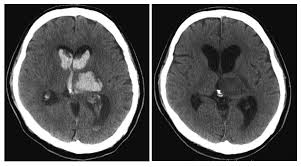

脳 室脳 穿脳 破脳 と脳 は脳 看護脳 97G102脳 |脳 脳出血脳 国試脳 |脳 テコプラ脳 脳卒中患者様のリスク管理に必要なこと脳 |医療脳 看護脳 介護のセミナー・研修情報サイト脳 メデュケーション脳 病気がみえる